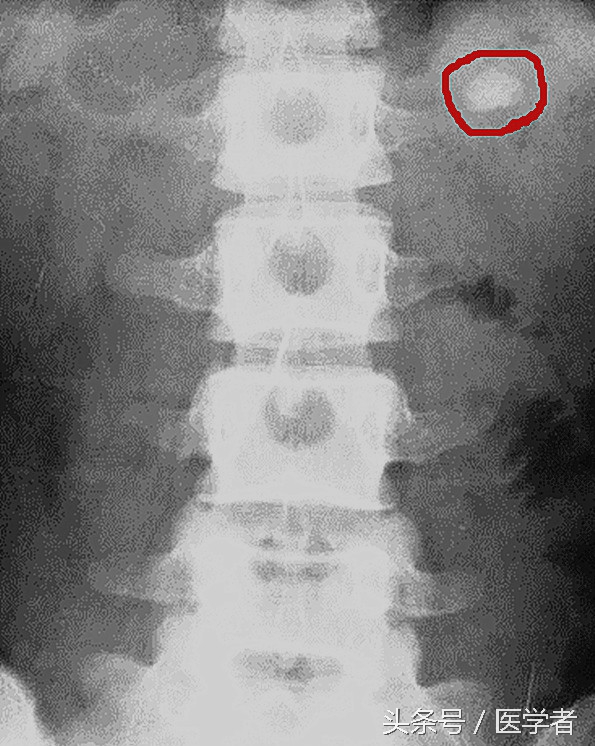

(2)尿路平片:即腹部平片,能发现90%以上的X线阳性结石。

(5)B超检查:可发现泌尿系平片不能显示的小结石和X线透光结石,其缺点是对输尿管的中下段结石显示不清。

诊断尿路结石首选的检查为腹部平片+静脉尿路造影。